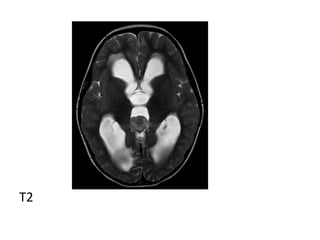

b) MRI -T1 :isointense or slightly hyperintense to adjacent brain -T2 : isointense or slightly hyperintense to adjacent brain, may have areas of cyst formation, central calcification appears low signal (engulfed pineal gland) -T1+C : vivid and homogeneous